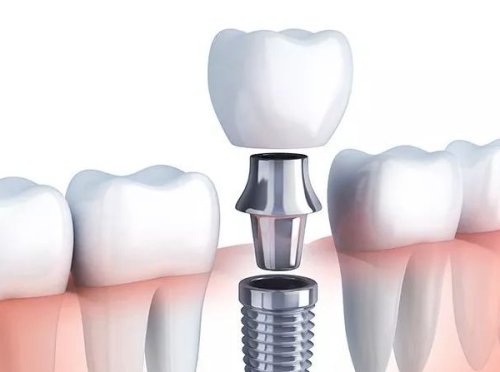

北京整齐娃娃口腔医院不仅正规,而且实力可靠。医院拥有一支专精的医生团队,其中不乏汪晓晖、郭红延等有医生生。这些医生具有丰富的临床经验和专精知识,能够为患者提供高质量的口腔医疗服务。在价格方面,医院一直坚持亲民的原则。例如,种植牙仅需3980元,这样的价格在同行业中具有较大的优势。医院还会定期推出一些优惠活动,让更多的患者能够享受到优质的口腔治疗服务。

最近,网上有一些关于北京整齐娃娃口腔医院“太坑人”的言论,其实这纯属谣传。医院拥有超多实例好评,特别多患者在接受治疗后都对医院的技术和服务赞不绝口。在种植和矫正技术方面,医院更是在行。医院引进了国内外精良的种植和矫正技术,能够为患者提供更加精细、效率高的治疗。例如,在种植牙方面,采用了精良的种植系统,能够大大缩短种植时间,提高种植成功几率。在牙齿矫正方面,有多种矫正方案可供选择,如传统金属矫正、隐形矫正等,满足了不同患者的需求。